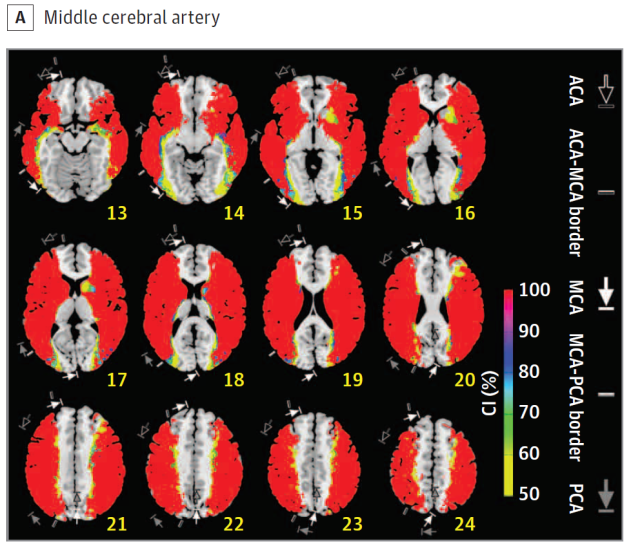

Middle

cerebral artery

Cerebral vascular territories